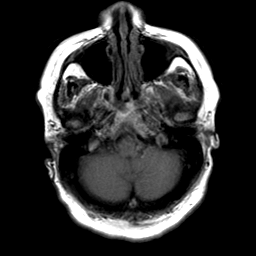

Cerebral hemorrhage, MR Study mr-t1 -- Slice #5

[Home][Help][Clinical] Slice 5